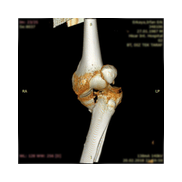

Görüntüleri büyütmek için resmin üstüne tıklayınız.